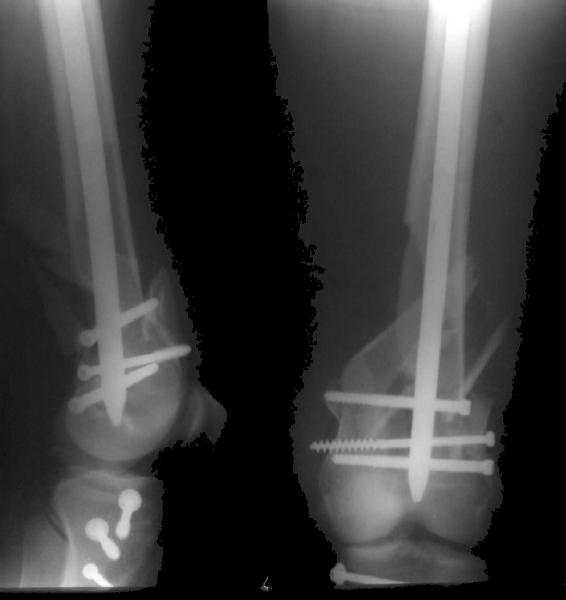

Re: Open supracondylar femur fx

Alexander Chelnokov 31 Октябрь 2004, 20:44

And why LISS is superior here than nail?

Look what we would have done.

I would not say that the LISS is superior to the nail. If I would, I had not post original mail. I wanted to generate discussion. Your option is a very viable one. I feel a little bit shaky the distal femur, but it is just gut feeling no science behind it. Any way nice fixation, congarts!